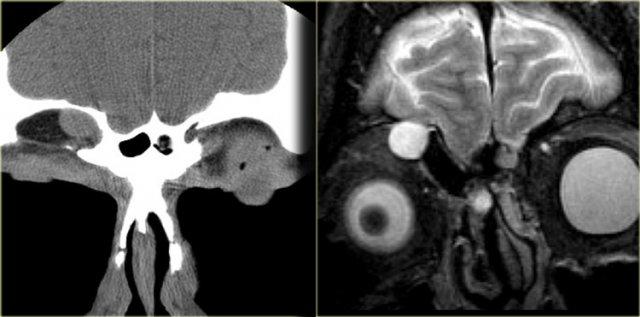

Ca bệnh bên trái minh họa hai biến chứng điển hình của chấn thương vùng mặt trán.

Gãy xương mũi hai bên là dấu hiệu gợi ý nguyên nhân chấn thương.

Quan sát hình CT ở ngoài cùng bên trái, bạn sẽ nhận thấy một khối mô mềm lồi trong xoang trán.

Hình MRI tương ứng cho thấy một cấu trúc tròn tăng tín hiệu ở cùng vị trí.

Hãy nghiên cứu kỹ các hình ảnh bên trái trước khi tiếp tục đọc.

Bây giờ hãy quan sát lại cẩn thận hình CT ở ngoài cùng bên trái.

Bạn có nhận thấy khuyết xương ở bên trái, tại bờ ngoài của khoang khí sàng (mũi tên vàng) không?

Hình MRI cho thấy có mô não tại vị trí khuyết xương này.

Bệnh nhân này có cả nang nhầy lẫn não thoát vị mắc phải.

Hai nguyên nhân phổ biến nhất gây nang nhầy là chấn thương và viêm mạn tính do tắc nghẽn lỗ thông xoang.